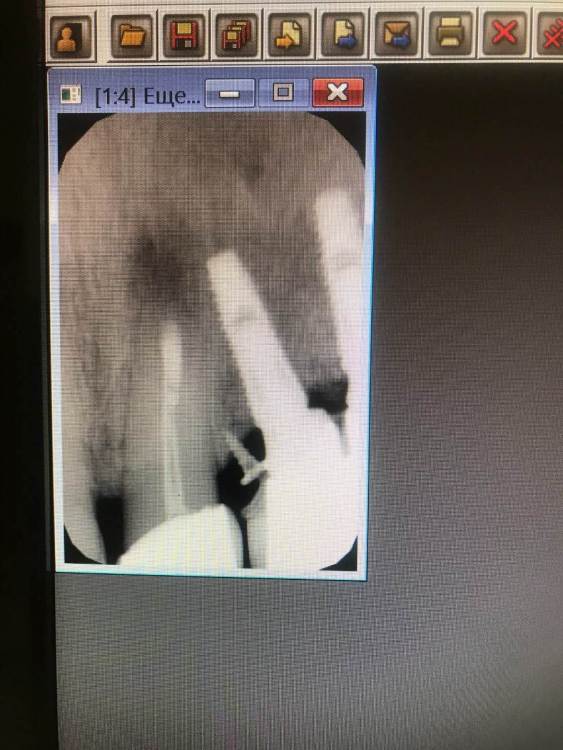

TIGER Опубликовано 1 октября, 2022 Поделиться Опубликовано 1 октября, 2022 Всем хорошего дня!Иногда некачественное эндо может привести к фатальным последствия,тут мы успели принять меры и сохранить и зуб и имплант!Вывод:эндо подготовка зубов прилегающих к зоне имплантации должна проводиться до имплантации!P.s винтик от НКР уже 7 лет там 3 Ссылка на комментарий

Женька Опубликовано 1 октября, 2022 Поделиться Опубликовано 1 октября, 2022 Классно получилось! По снимку до вроде эндо было? Ссылка на комментарий

TIGER Опубликовано 1 октября, 2022 Автор Поделиться Опубликовано 1 октября, 2022 @Женька Спасибо,да было,когда делали давно Ссылка на комментарий